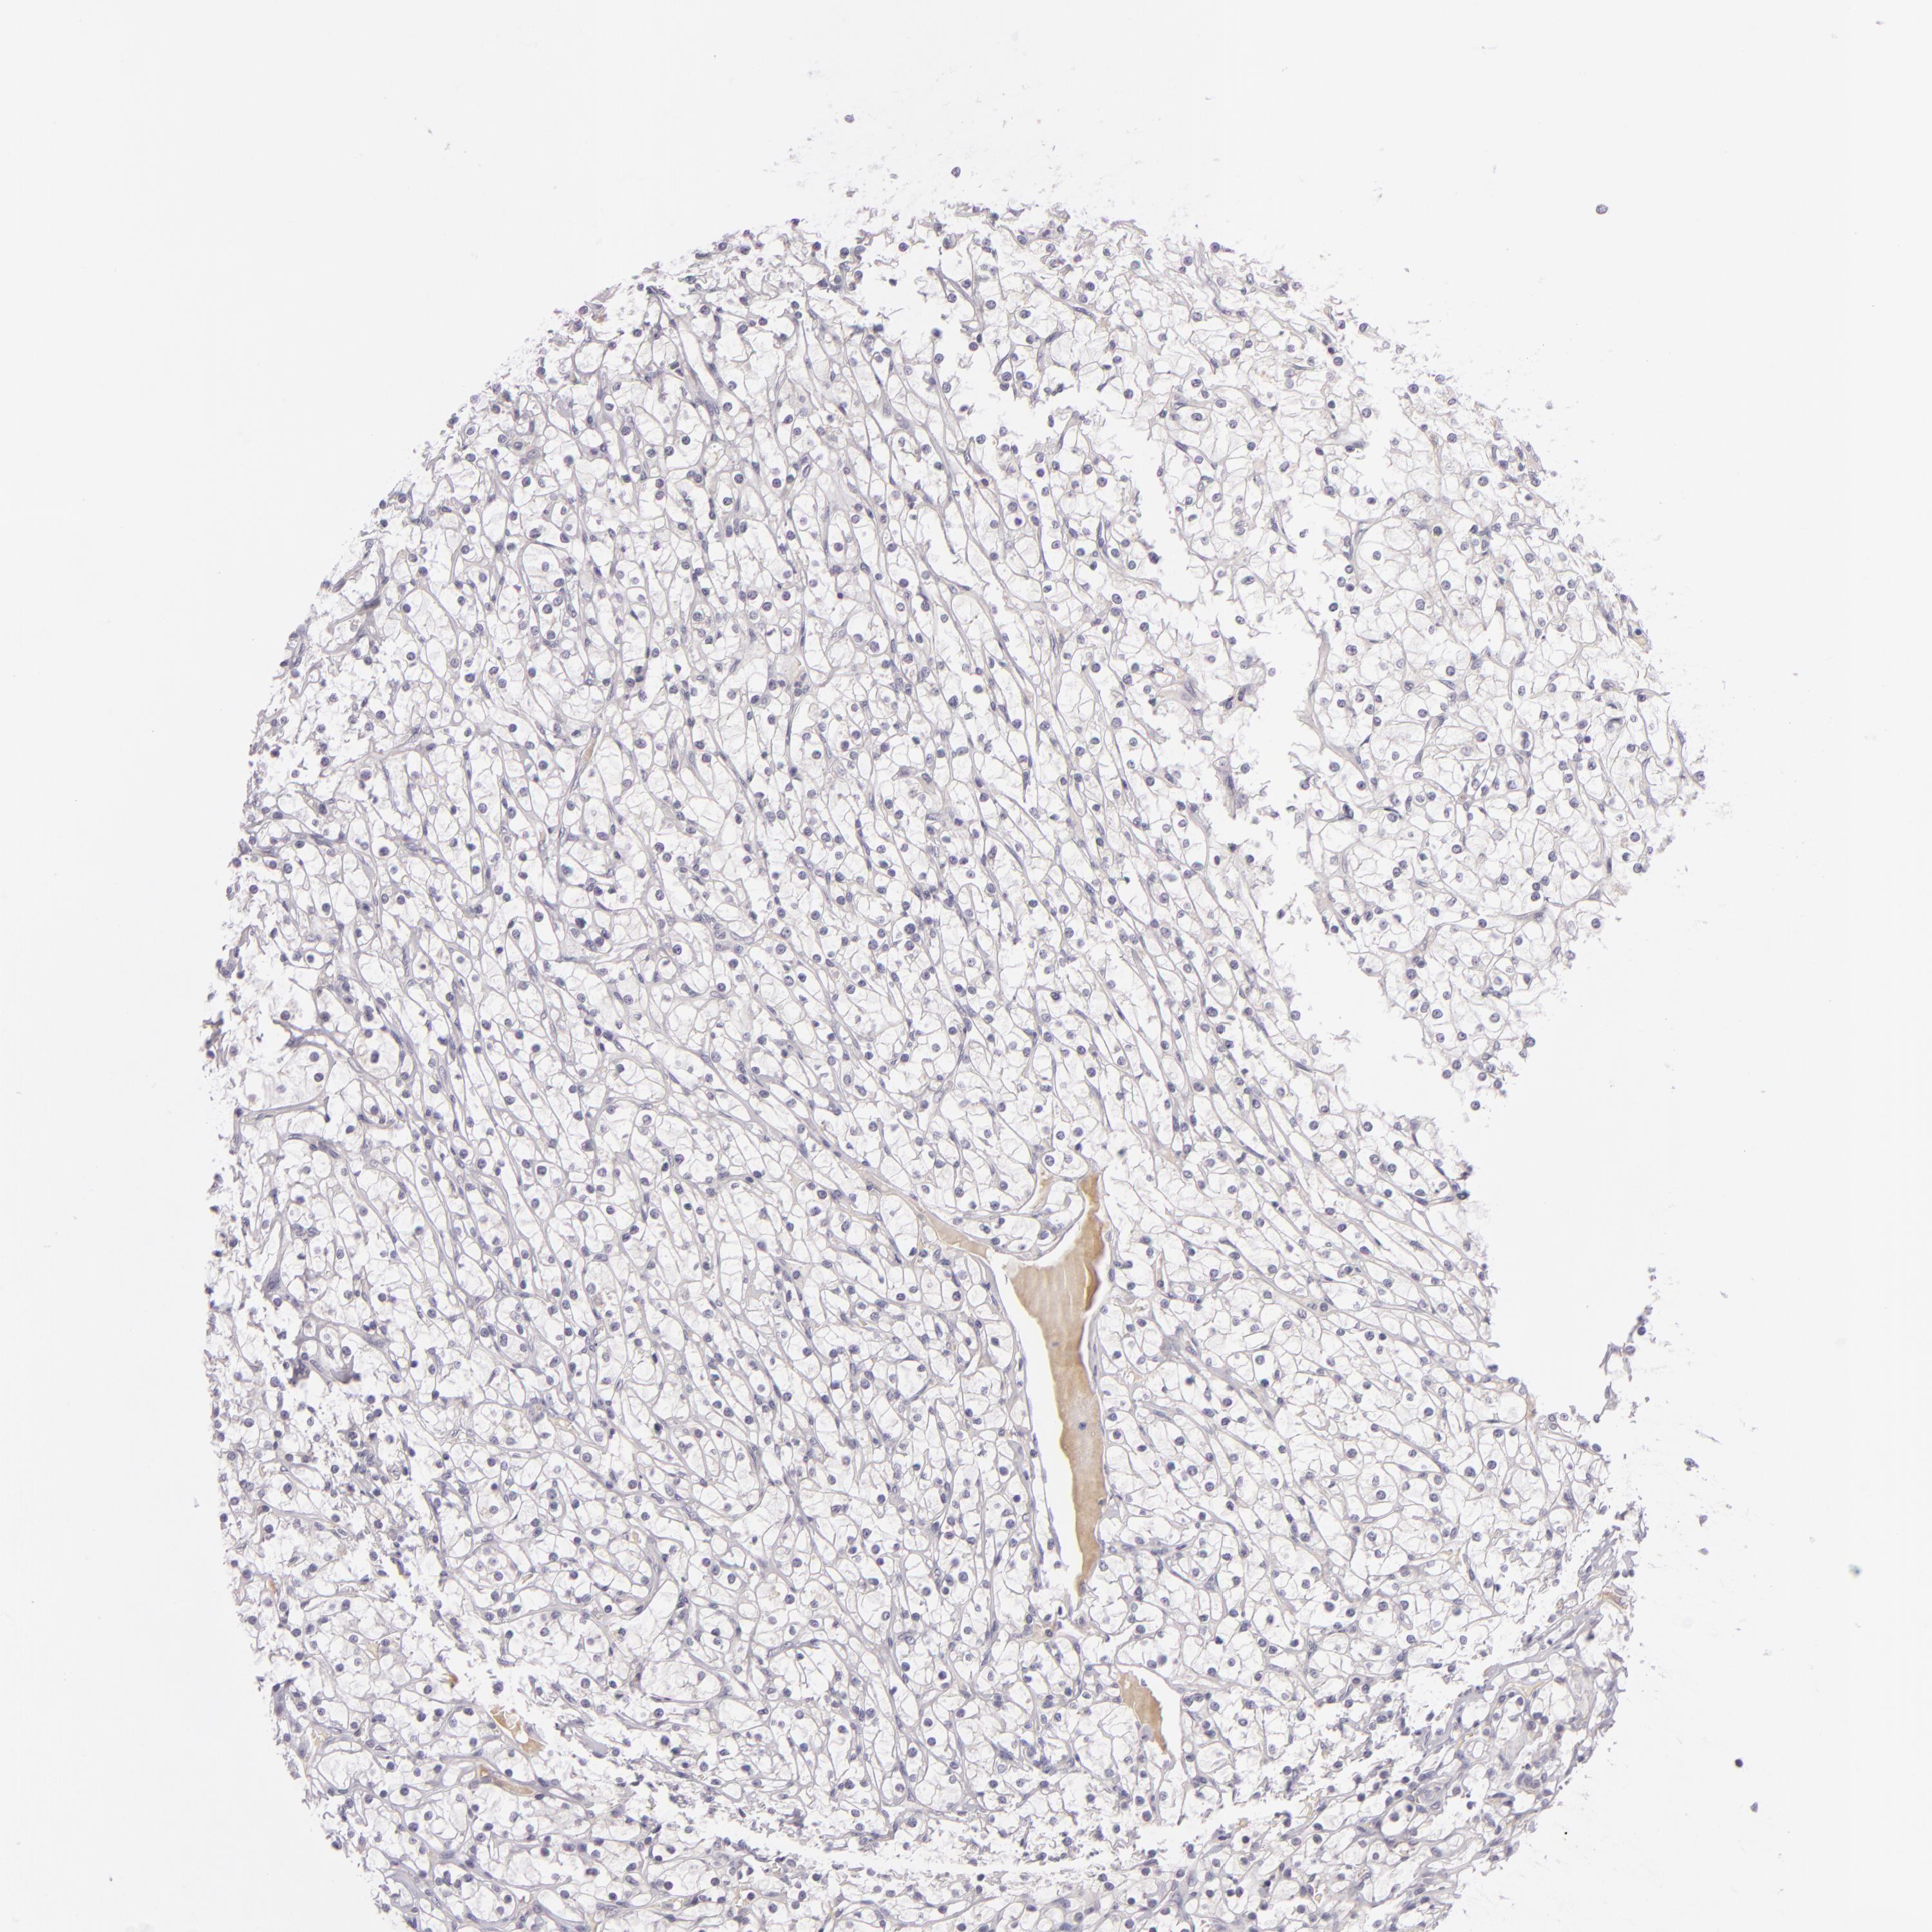

KIDNEY RENAL CLEAR CELL CARCINOMA (TCGA) - Interactive survival scatter ploti

The Survival Scatter plot shows the clinical status (i.e. dead or alive) for all individuals in the patient cohort, based on the same data that underlies the corresponding Kaplan-Meier plots. Patients that are alive at last time for follow-up are shown in blue and patients who have died during the study are shown in red.

The x-axis shows the expression levels (FPKM) of the investigated gene in the tumor tissue at the time of diagnosis. The y-axis shows the follow-up time after diagnosis (years). Both axes are complimented with kernel density curves demonstrating the data density over the axes. The top density plot shows the expression levels (FPKM) distribution among dead (red) and alive patients (blue). The right density plot shows the data density of the survived years of dead patients with high and low expression levels respectively, stratified using the cutoff indicated by the vertical dashed line through the Survival Scatter plot. This cutoff is automatically defined based on the FPKM cutoff that minimizes the p-score. The cutoff can be changed by dragging the vertical line or by entering a cutoff value in the square labeled "Current cut-off".

Under the Survival Scatter plot the p-score landscape (black curve; left axis) is shown together with dead median separation (red curve; right axis). Dead median separation is the difference in median mRNA expression between patients who have died with high and low expression, respectively. It is calculated as follows: median FPKM expression of dead patients with high expression - median FPKM expression of dead patients with low expression. This is intended to aid the user in visually exploring custom cutoffs and the associated p-scores and dead median separation.

Individual patient data is displayed and can be filtered by clicking on one or more of the category buttons on the top of the page. Categories describing expression level and patient information include: high, low, alive, dead, female, male and tumor stages. The scale of the x-axis can be toggled between linear and log-scale by clicking on the "x log" button. Mouse-over function shows TCGA ID, patient information and mRNA expression (FPKM) for each patient.

& Survival analysisi

Kaplan-Meier plots summarize results from analysis of correlation between mRNA expression level and patient survival. Patients were divided based on level of expression into one of the two groups "low" (under cut off) or "high" (over cut off). X-axis shows time for survival (years) and y-axis shows the probability of survival, where 1.0 corresponds to 100 percent.

DAG1 is not prognostic in Kidney Renal Clear Cell Carcinoma (TCGA)

Best expression cut offi

Based on the FPKM value of each gene, patients were classified into two groups and association between prognosis (survival) and gene expression (FPKM) was examined. The best expression cut-off refers the FPKM value that yields maximal difference with regard to survival between the two groups at the lowest log-rank P-value. Best expression cut-off was selected based on survival analysis .

When clicking on this number, the vertical dashed line indicating cut-off, the interactive survival plot, and the Kaplan-Meier curve will be adjusted to show results based on the best expression cut-off.

: 20.7

P scorei

Log-rank P value for Kaplan-Meier plot showing results from analysis of correlation between mRNA expression level and patient survival.

N/A

TCGA RNA samplesi

RNA-seq data is reported as average FPKM (number Fragments Per Kilobase of exon per Million reads), generated by the The Cancer Genome Atlas (TCGA) .

Normal distribution across the dataset is visualized with box plots, shown as median and 25th and 75th percentiles. Points are displayed as outliers if they are above or below 1.5 times the interquartile range. FPKM values of the individual samples are presented next to the box plot.

Average pTPM 27.5

Number of samples 521